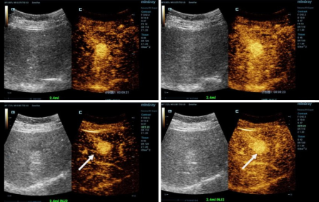

![more-precise-diagnoses-with-hifr-ceus.thumb.319.319 HiFR CEUS? ?? ?? ??? ??]() HiFR CEUS? ?? ?? ??? ??CEUS(?? ?? ???)? ?? ???? ???? ?? ? ? ?? ?? ???? ?? ??? ?? ???????. ??? ?? ? ??? ?? ????? ?? 10? ? ?? ??? ??? ??? ? ?? HiFR CEUS(????? ?? ?? ???)???.??? | ?? ?? 2022-12-16

HiFR CEUS? ?? ?? ??? ??CEUS(?? ?? ???)? ?? ???? ???? ?? ? ? ?? ?? ???? ?? ??? ?? ???????. ??? ?? ? ??? ?? ????? ?? 10? ? ?? ??? ??? ??? ? ?? HiFR CEUS(????? ?? ?? ???)???.??? | ?? ?? 2022-12-16